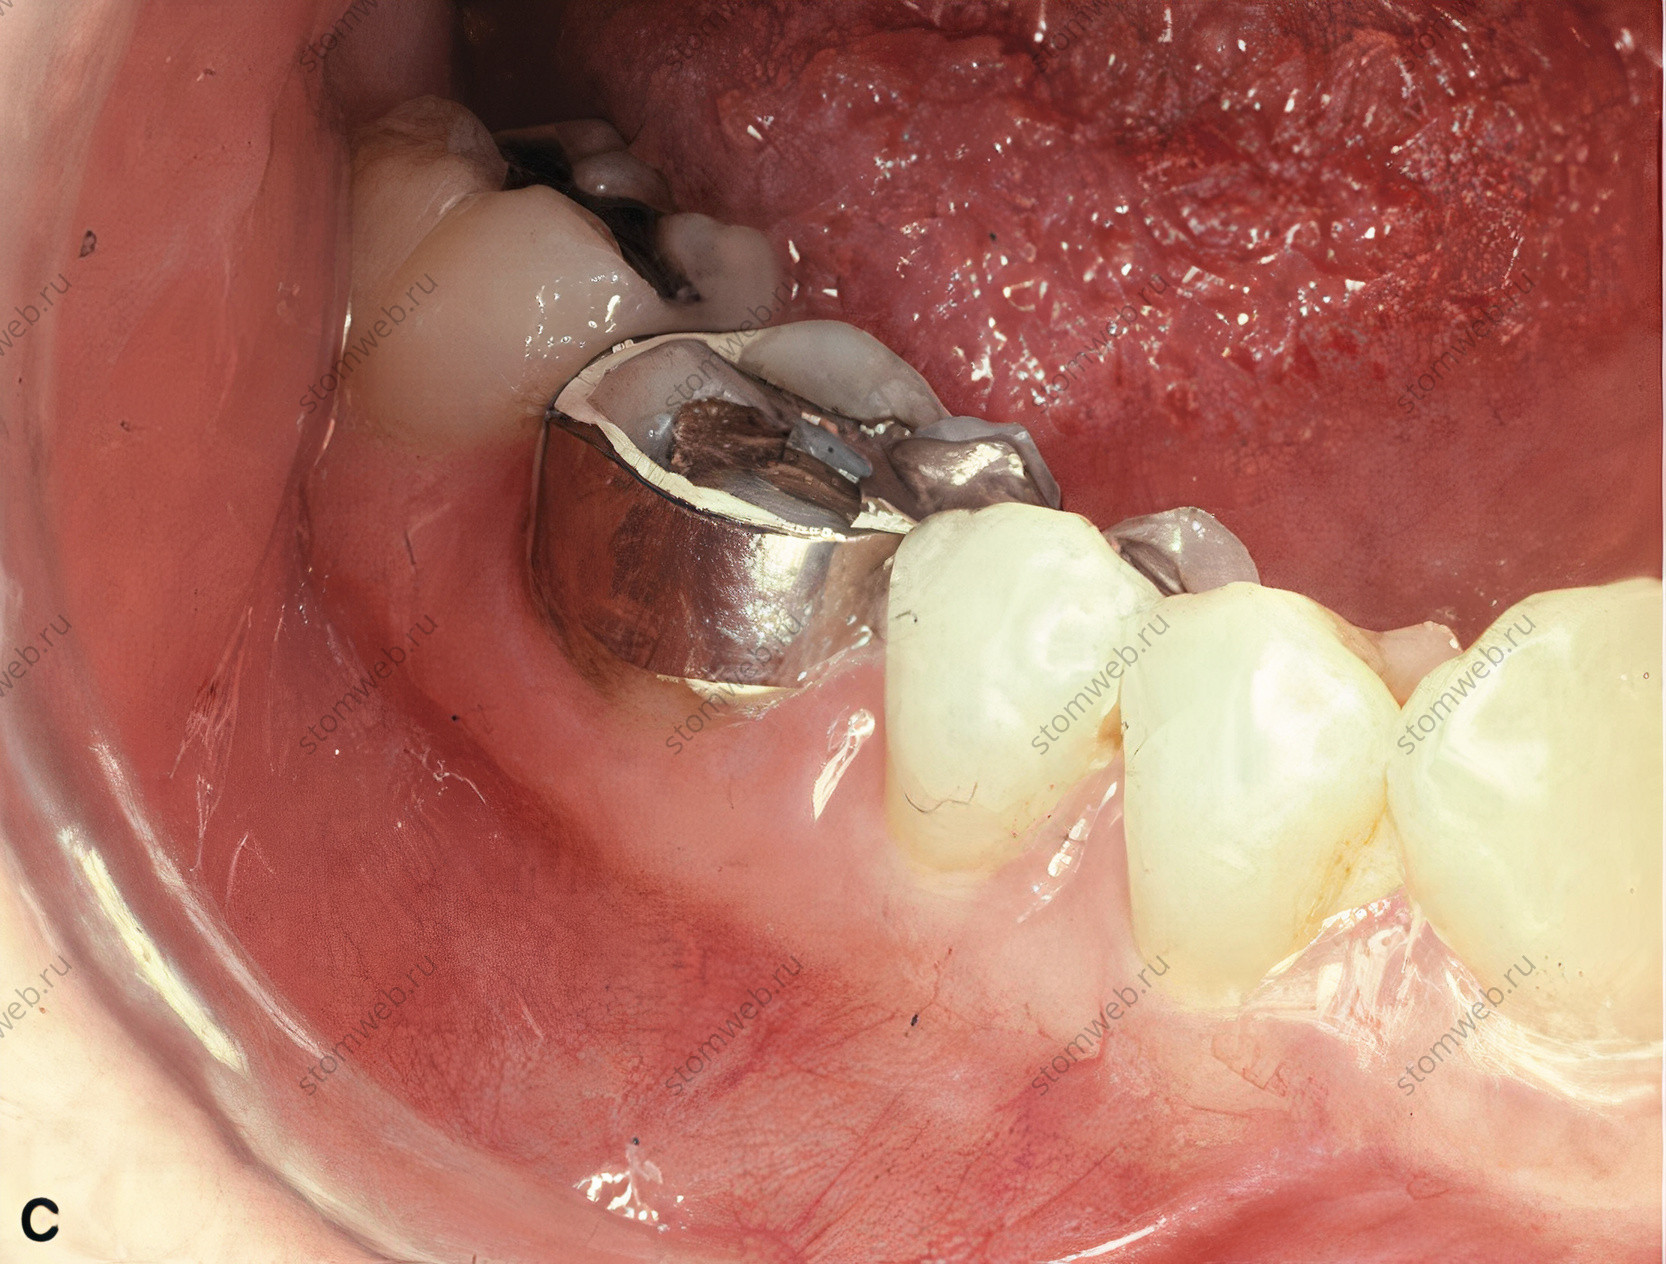

Рисунок 19 Диагностическое бандажирование зуба с трещиной коронки. A. Рентгенограмма первого моляра нижней челюсти с симптоматической трещиной коронки на дистальной стороне зуба. Поскольку линия перелома находится в мезио-дистальной ориентации, на снимке она не видна. Б. При диагностике (на основании симптомов и клинических данных) обратимого пульпита на зуб цементируют кольцо. C. Фотография сделана через 2 недели, когда пациент сообщает о полном отсутствии симптомов. Теперь пациенту может быть предложен вариант коронки с полным покрытием с информированием о том, что около 20% таких зубов могут потребовать эндодонтического лечения позже; некоторые пациенты могут предпочесть профилактическое лечение корневых каналов перед установкой коронки.